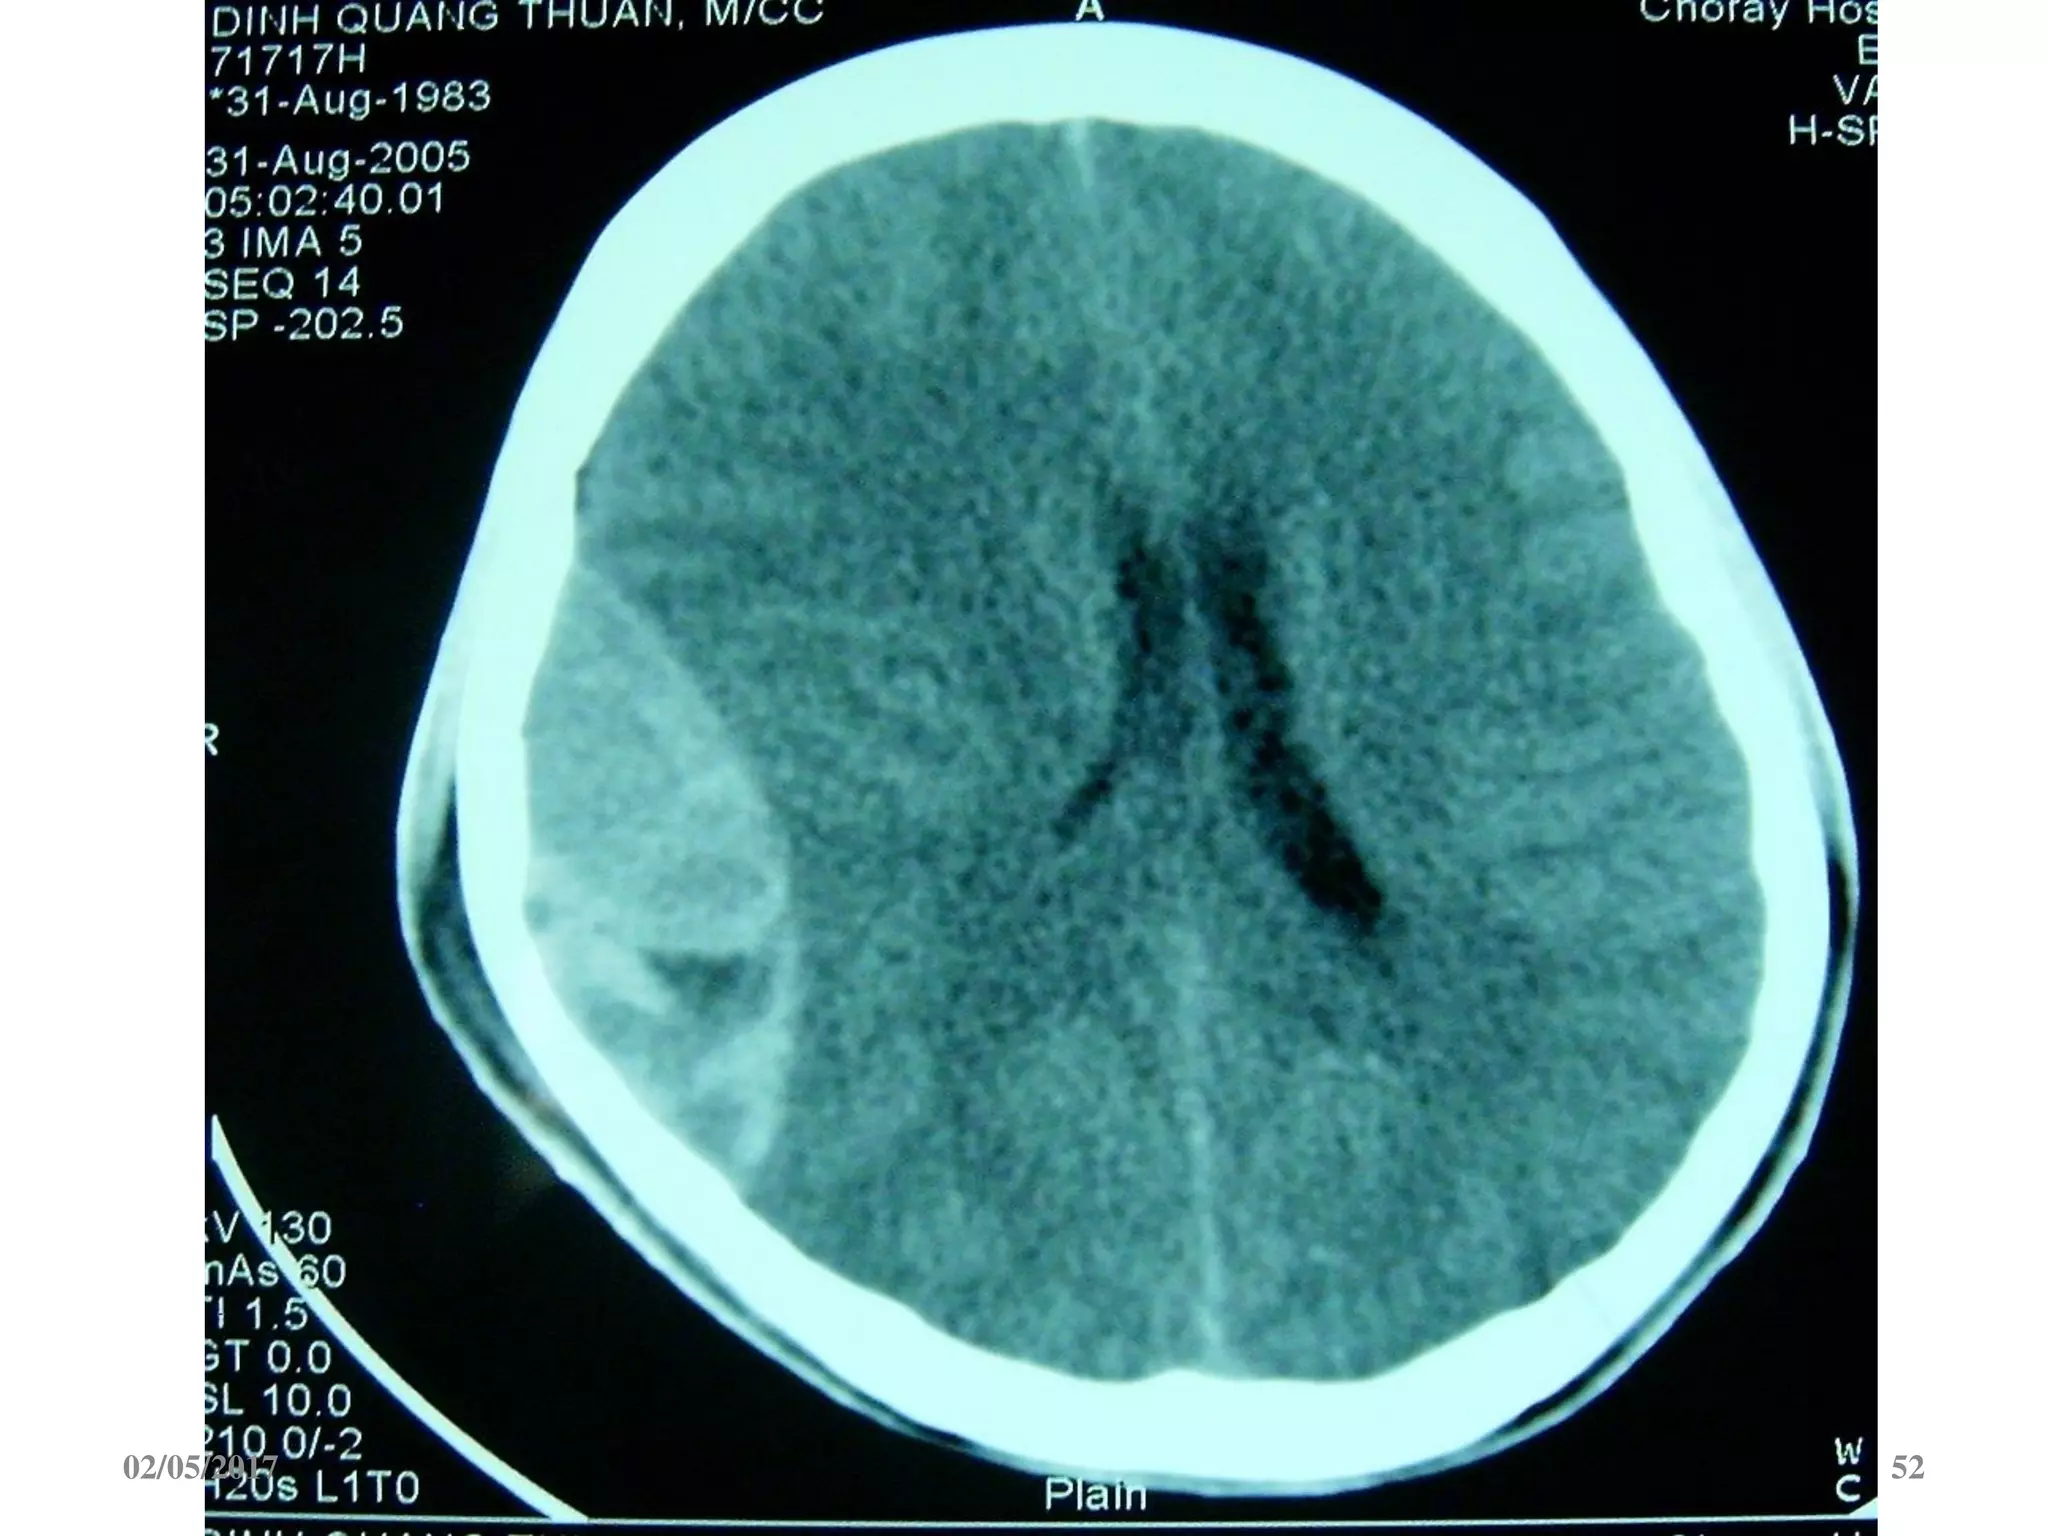

Máu tụ dưới màng cứng cấp

 Ngoài trục, hình liềm,

tăng đậm độ

 Vượt qua được các

khớp sọ

 Thường kèm dập não

02/05/2017 54

02/05/2017 55